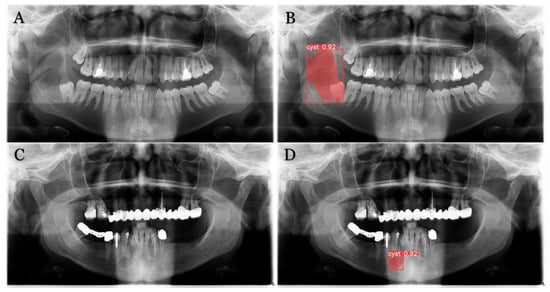

The trained model is capable of predicting bounding boxes, segmentation masks and probabilities, as shown in Figure 4 and Figure 5.

Figure 5. Model segmentation predictions of the lesions. Radiolucent mandibular lesions seen on panoramic radiographs shown on (A,C). Successful model segmentation with 92% shown on (B,D).